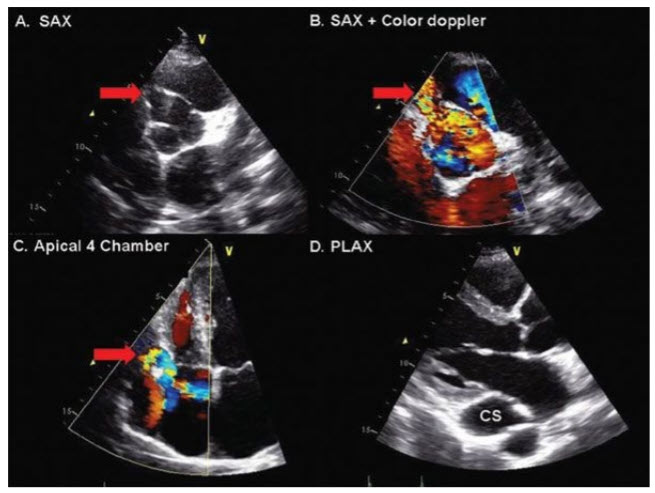

Spontaneous closure rarely occurs. Coronary fistulae rarely close spontaneously. The most common origin of coronary arteriovenous fistula is the right coronary artery, with a fistulous communication into the RV, RA, or coronary sinus (appearance on echocardiography demonstrated on the next page). Less commonly, it empties into the LV, LA, or PA. Complications may include CHF from left-to-right shunt, bacterial endocarditis, coronary ischemia, and rupture or thrombosis of the fistula. Surgical closure is associated with a good outcome (figure below).

The right coronary artery fistula (red arrow) is seen in transthoracic short- axis (SAX) views arising from the right coronary cusp of the aortic valve (A) confirmed with color flow Doppler (B). In this case, the right coronary fistula drained into the right atrium (C) via a dilated coronary sinus (D). PLAX, parasternal long axis.